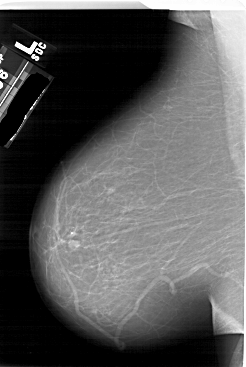

A_1623_1.LEFT_MLO

LEFT_MLO LINES 6601 PIXELS_PER_LINE 4426 BITS_PER_PIXEL 12 RESOLUTION 43.5 NON_OVERLAY